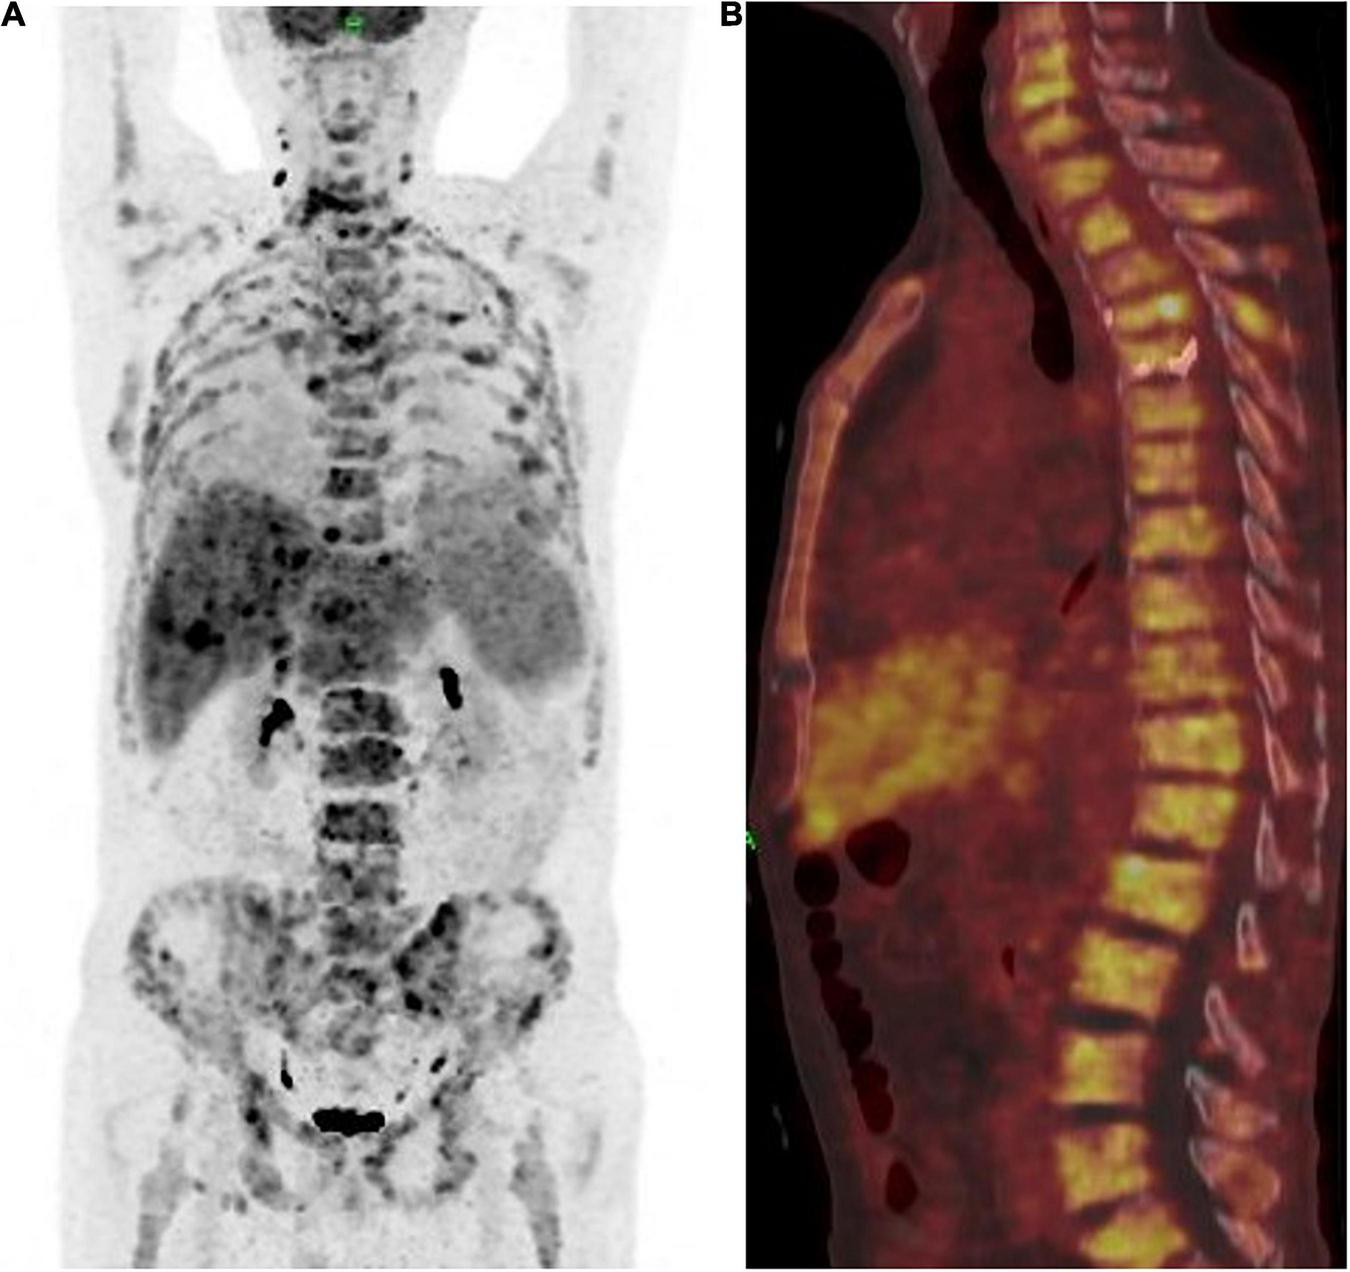

A 63-year-old male who was diagnosed with eczema of the scrotum in 2012 and did not pursue treatment visited our hospital on 12th October, 2020 on account of back pain. Positron emission tomography computed tomography (PET-CT) showed erosion and metastatic nodules in the occipital bone, entire vertebra, bilateral ribs, appendicular skeleton and the pelvic bone (Figures 1A,B). The patient was also positive for hepatitis B, and the serum levels of CA19.9, AFP, NSE, and CEA were 43.24 U/ml, 2.90 ng/ml, 15.62 ng/L, and 1,488 ng/ml, respectively. Fine-needle aspiration cytology (FNAC) was performed on the hepatic metastatic node and right groin lymph node, and the biopsies indicated neuroendocrine differentiation. However, based on the clinical presentation and case history, we suspected that the primary tumor was eczema of scrotum (Figure 2). Perineal skin mass resection surgery was subsequently performed, and histological examination of the epidermis and dermis revealed lightly stained tumor cells with dense cytoplasm that were arranged in the form of sheets, small nests or scattered masses. These histological features were consistent with Paget’s disease with infiltrating adenocarcinoma. The tumor grew 0.4 cm deep into the dermis and involved the skin appendages. Immunohistochemical staining indicated that the EMPD tumor cells were positive for GATA3 (3+), CK7 (3+), GCDFP15 (1+), androgen receptor (2+), HER2 (2+), ER (1+), CEA (3+), and synaptophysin (focal+), and negative for CK20, P16, S-100, HMB-45, P40, PR, CD56, and ChrA. However, the FISH test for HER2 was negative (Figure 3). Based on the histopathological and immunohistochemical findings, we diagnosed the case as cT1N2M1 primary EMPD with neuroendocrine differentiation on 20th October, 2020.

FIGURE 1

(A) Positron emission tomography and computed tomography (PET-CT) showed a multiple bone destruction with bone metastases including whole vertebra, occipital bone, ribs of double side, appendicular skeleton, and pelvis. (B) PET-CT showed a whole vertebra metastatic Primary EMPD, showing that a most obvious SUV of 18.9.

The patient achieved partial response (PR) for the metastatic lesions according to the mRECIST1.1 criteria after four cycles of treatment. The total PET-CT scan (Figures 4A,B), showed an obvious decrease in SUV from 18.9 to 5.3, and the serum level of CEA also dropped within the normal range. Computed tomography (CT) and magnetic resonance imaging (MRI) showed that both hepatic and lymph node (regional and distant) metastases achieved stable disease (SD) status as per RECIST1.1. However, the patient developed fractures in the fourth and fifth thoracic vertebrae during the treatment period due to an accident. Therefore, the treatment regimen was suspended for 4 weeks and percutaneous vertebroplasty was performed in that interval. External thoraco-lumbosacral orthosis was used postoperatively.

FIGURE 4

(A) Positron emission tomography and computed tomography showed the patient achieved partial response (PR) according to the mRECIST1.1 on metastatic lesions. (B) PET-CT showed a whole vertebra metastatic Primary EMPD, showing that a most obvious decrease of SUV from 18.9 to 5.3.